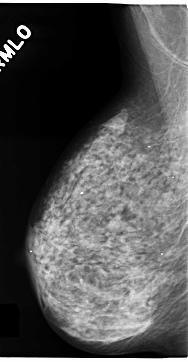

C_0158_1.RIGHT_MLO

RIGHT_MLO LINES 4704 PIXELS_PER_LINE 2440 BITS_PER_PIXEL 12 RESOLUTION 50 NON_OVERLAY